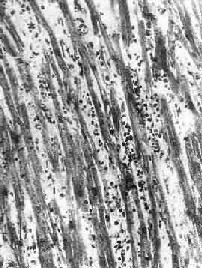

图8-41 病毒性心肌炎

心肌间质内有弥漫性淋巴细胞及组织细胞浸润

本病病变依患者年龄不同而有所不同。妊娠最初3个月的胎儿感染风疹病毒时,可引起心内膜下心肌的无反应性心肌细胞坏死。在妊娠后期,胎儿感染柯萨奇病毒时则可引起全心炎,大多伴有心骨膜纤维弹性组织增生。初生儿的病毒性心肌炎可见到心肌细胞坏死及粒细胞浸润。其后,代之以巨噬细胞、淋巴细胞、浆细胞浸润及肉芽组织形成(图8-41)。在成人,多累及心房后壁、室间隔及心尖区,有时可累及传导系统。镜下,主要病变为坏死性心肌炎。晚期,可见到明显的心肌间质纤维化,伴有代偿性心肌肥大及心腔扩张(充血性心肌病)。